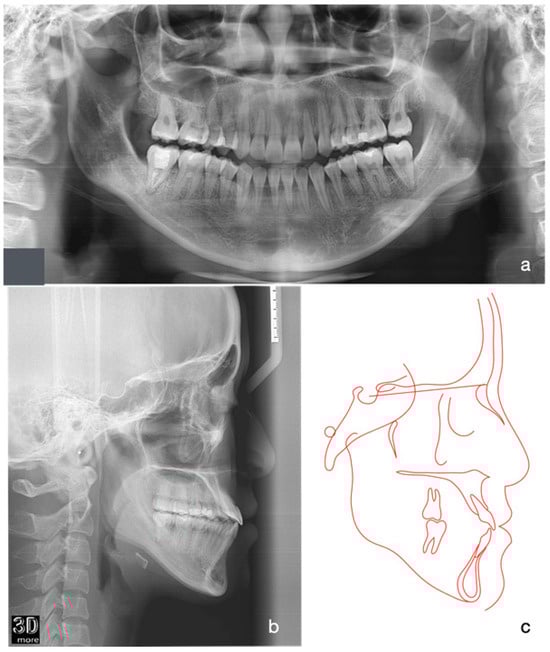

2.1. Diagnosis and Aetiology

| SNA | 81° ± 3° | 81° | 81.5° | 81° |

| SNB | 78° ± 3° | 83.5° | 81.5° | 81.5° |

| ANB | 3° ± 2° | −2.5° | 0° | −0.5° |

| Maxillary inclination (S-N/ANS-PNS) | 8° ± 3° | 8° | 8° | 8° |

| MMPA | 27° ± 3° | 28° | 31° | 30° |

| LFH % | 55% ± 2% | 58.5% | 58.7% | 58.6% |

| Upper incisor to Max. plane | 108° ± 6° | 126.5° | 126.5° | 126° |

| Lower incisor to Mand. Plane | 93° ± 6° | 94° | 92° | 83° |

| Lower incisor to A-Po line | 1 ± 1 mm | +12.5 mm | +8 mm | +5 mm |

| Inter-incisal angle | 133° ± 10° | 111° | 110° | 120° |

| Upper lip-E line | −2 ± 2 mm | −3 mm | −2 mm | −3 mm |

| Lower lip-E line | 0 ± 2 mm | +4 mm | +3 mm | −1 mm |